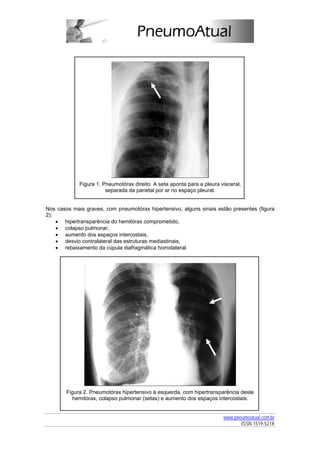

A radiografia de tórax em incidência póstero-anterior (PA), em posição ortostática, mostra

ausência de trama vascular pulmonar, com uma linha (a pleura visceral), em geral paralela à

Figura 1. Pneumotórax direito. A seta aponta para a pleura visceral,

separada da parietal por ar no espaço pleural.

Nos casos mais graves, com pneumotórax hipertensivo, alguns sinais estão presentes (figura

2):

• hipertransparência do hemitórax comprometido,

• colapso pulmonar,

• aumento dos espaços intercostais,

• desvio contralateral das estruturas mediastinais,

• rebaixamento da cúpula diafragmática homolateral.

Figura 2. Pneumotórax hipertensivo à esquerda, com hipertransparência deste

hemitórax, colapso pulmonar (setas) e aumento dos espaços intercostais.